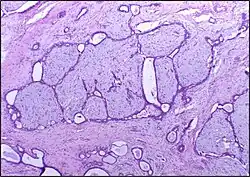

![]() |

Follicular lymphoma | Micrograph showing a small B-cell lymphoma compatible with follicular lymphoma. H&E stain. | Category: Histopathology of follicular lymphoma | Follicular lymphoma |